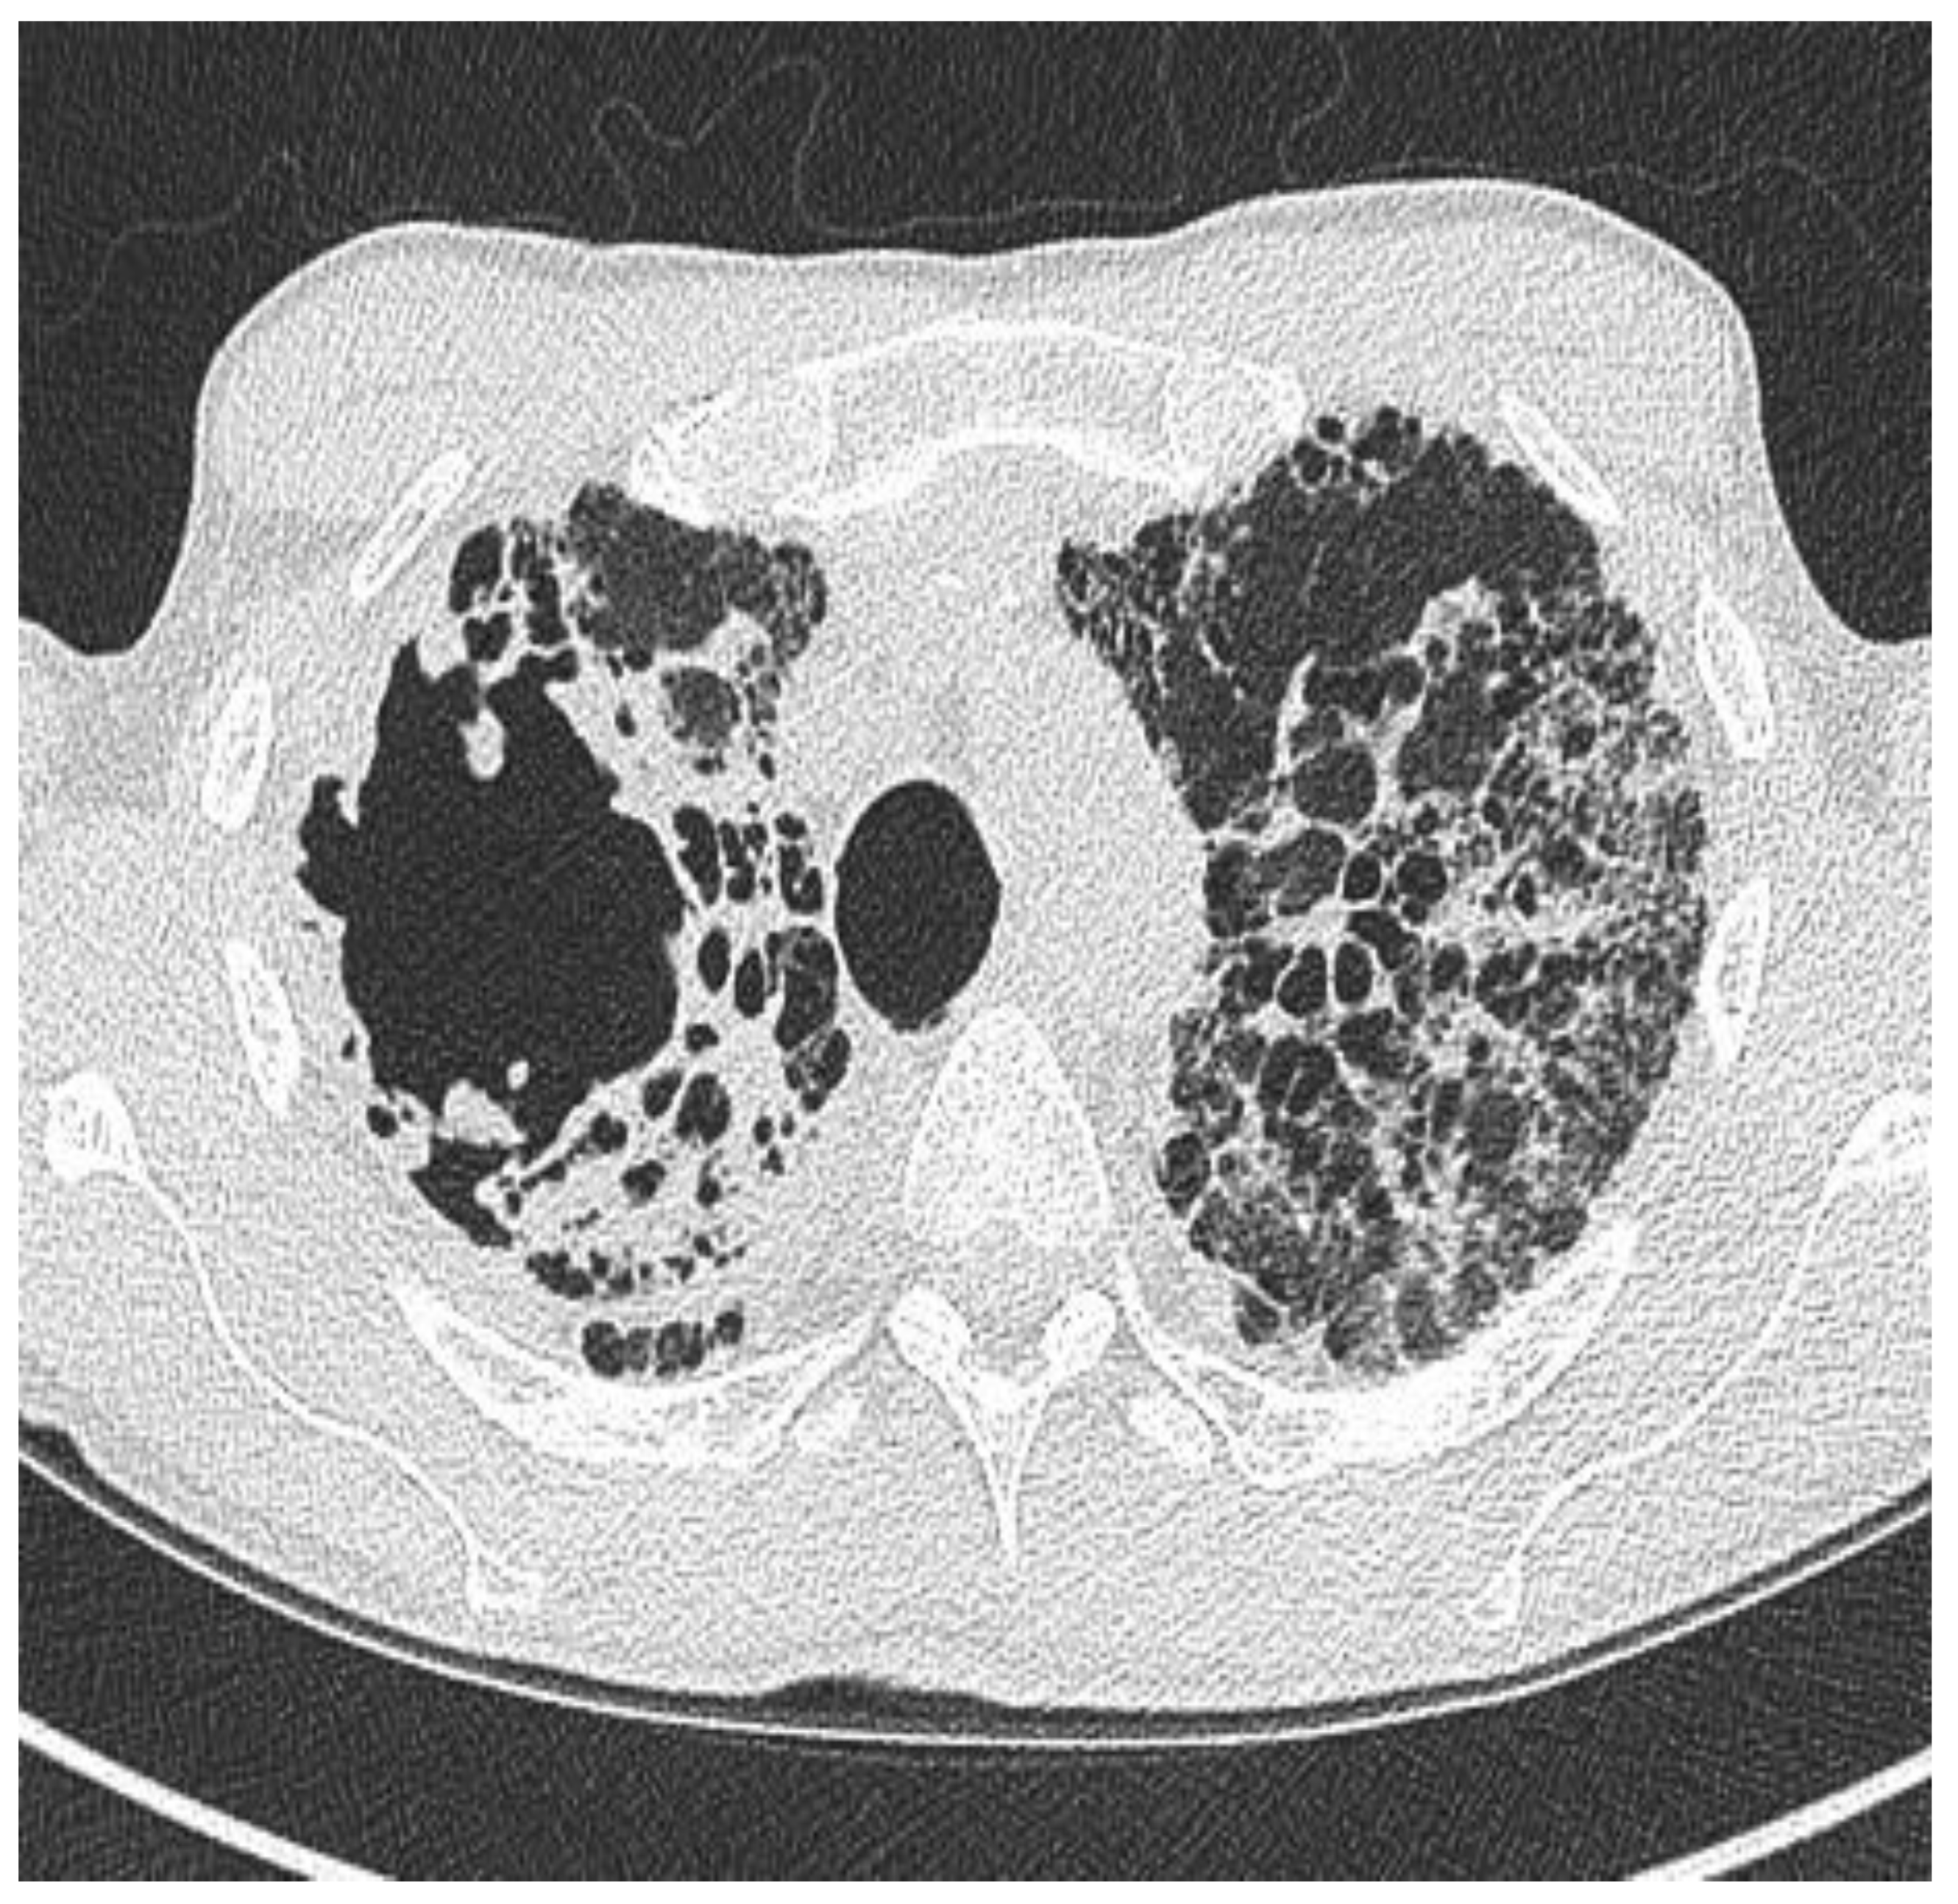

2.1. Clinical Phenotype by Radiology